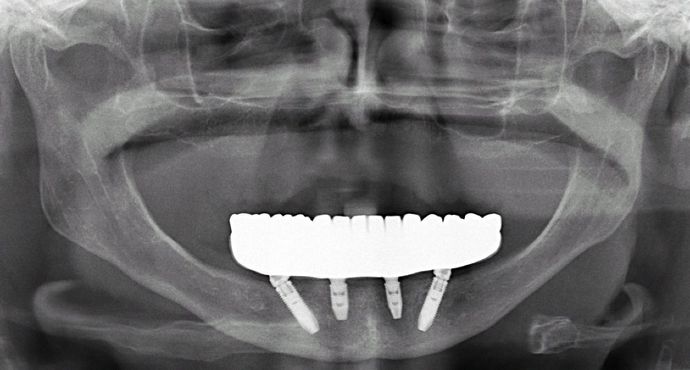

All-on-4/ Full Mouth Dental Implants / Teeth in a Day: Case 5- BB- Upper full denture and lower All-on-4 implant bridge

This lady had been wearing an upper denture for almost 40 years that worked well for her, but she was very unhappy with her lower partial that affected her ability to chew and speak well and be comfortable. Her failing lower teeth were removed and she was provided permanent teeth the same day with the All on 4 procedure.

Procedures : extractions, implants, All on 4 , Teeth in a day, no bone grafting and new upper full denture, lower monolithic zirconia bridge.